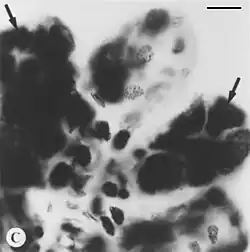

| Black and white Feulgen stained microphotograph depicting intact tick salivary glands infected by deer tick virus. Hypotrophied salivary acinus filled with amorphous masses of pinkstaining (=Feulgen positive) material (arrows). Scale bar = 10 µm. | |